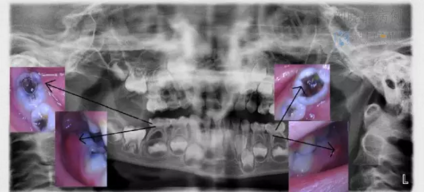

真相解密:寶寶乳牙要?dú)⑸窠?jīng)?關(guān)于乳牙根管治療史上最強(qiáng)圖解

寶寶牙齒疼得不行,去醫(yī)院找牙醫(yī)就診,經(jīng)??梢月?tīng)到這樣的兩種回答:“孩子的這顆牙齒需要?dú)⑸窠?jīng)了”“孩子的這顆牙齒需要做根管治療了”...

為了能夠幫助粑粑麻麻更好的解除疑惑,小科以一則漫畫形式給家長(zhǎng)科普一下乳牙根管治療的相關(guān)知識(shí)。

12.png

醫(yī)生不是掃描儀,也沒(méi)有透視眼,為了解患牙的牙根形態(tài)、走向、長(zhǎng)度及根尖周有無(wú)病變及病變大小,醫(yī)生常常要求患牙在根管治療術(shù)前,術(shù)中和術(shù)后分別拍X線片,以幫助診療。